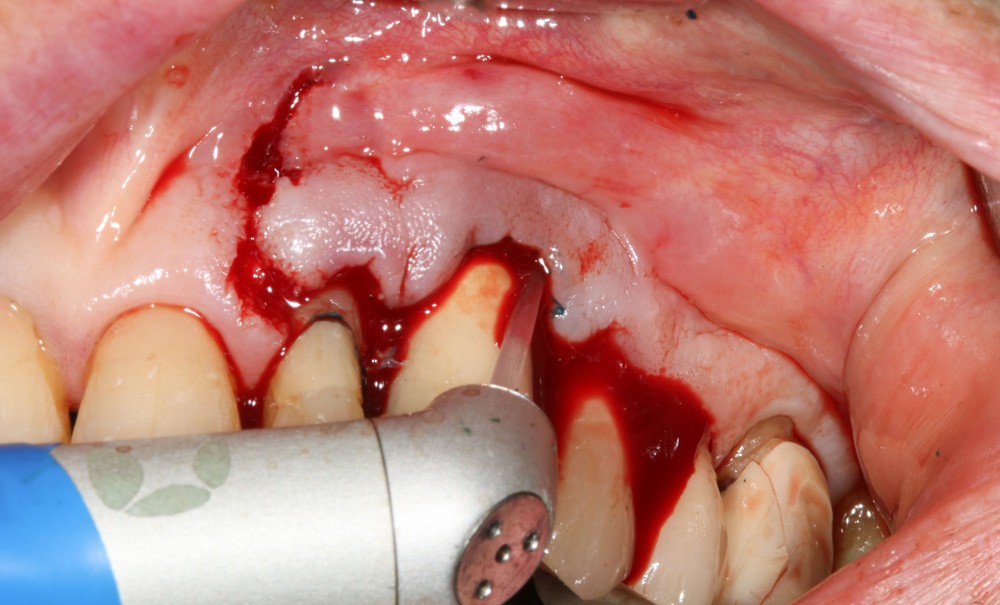

Le patient

- 70 ans

- Pas d’antécédents médicaux

- Ne fume pas

- Hygiène correcte

L’implant

- Site 23

- Mis en place il y a 12 ans